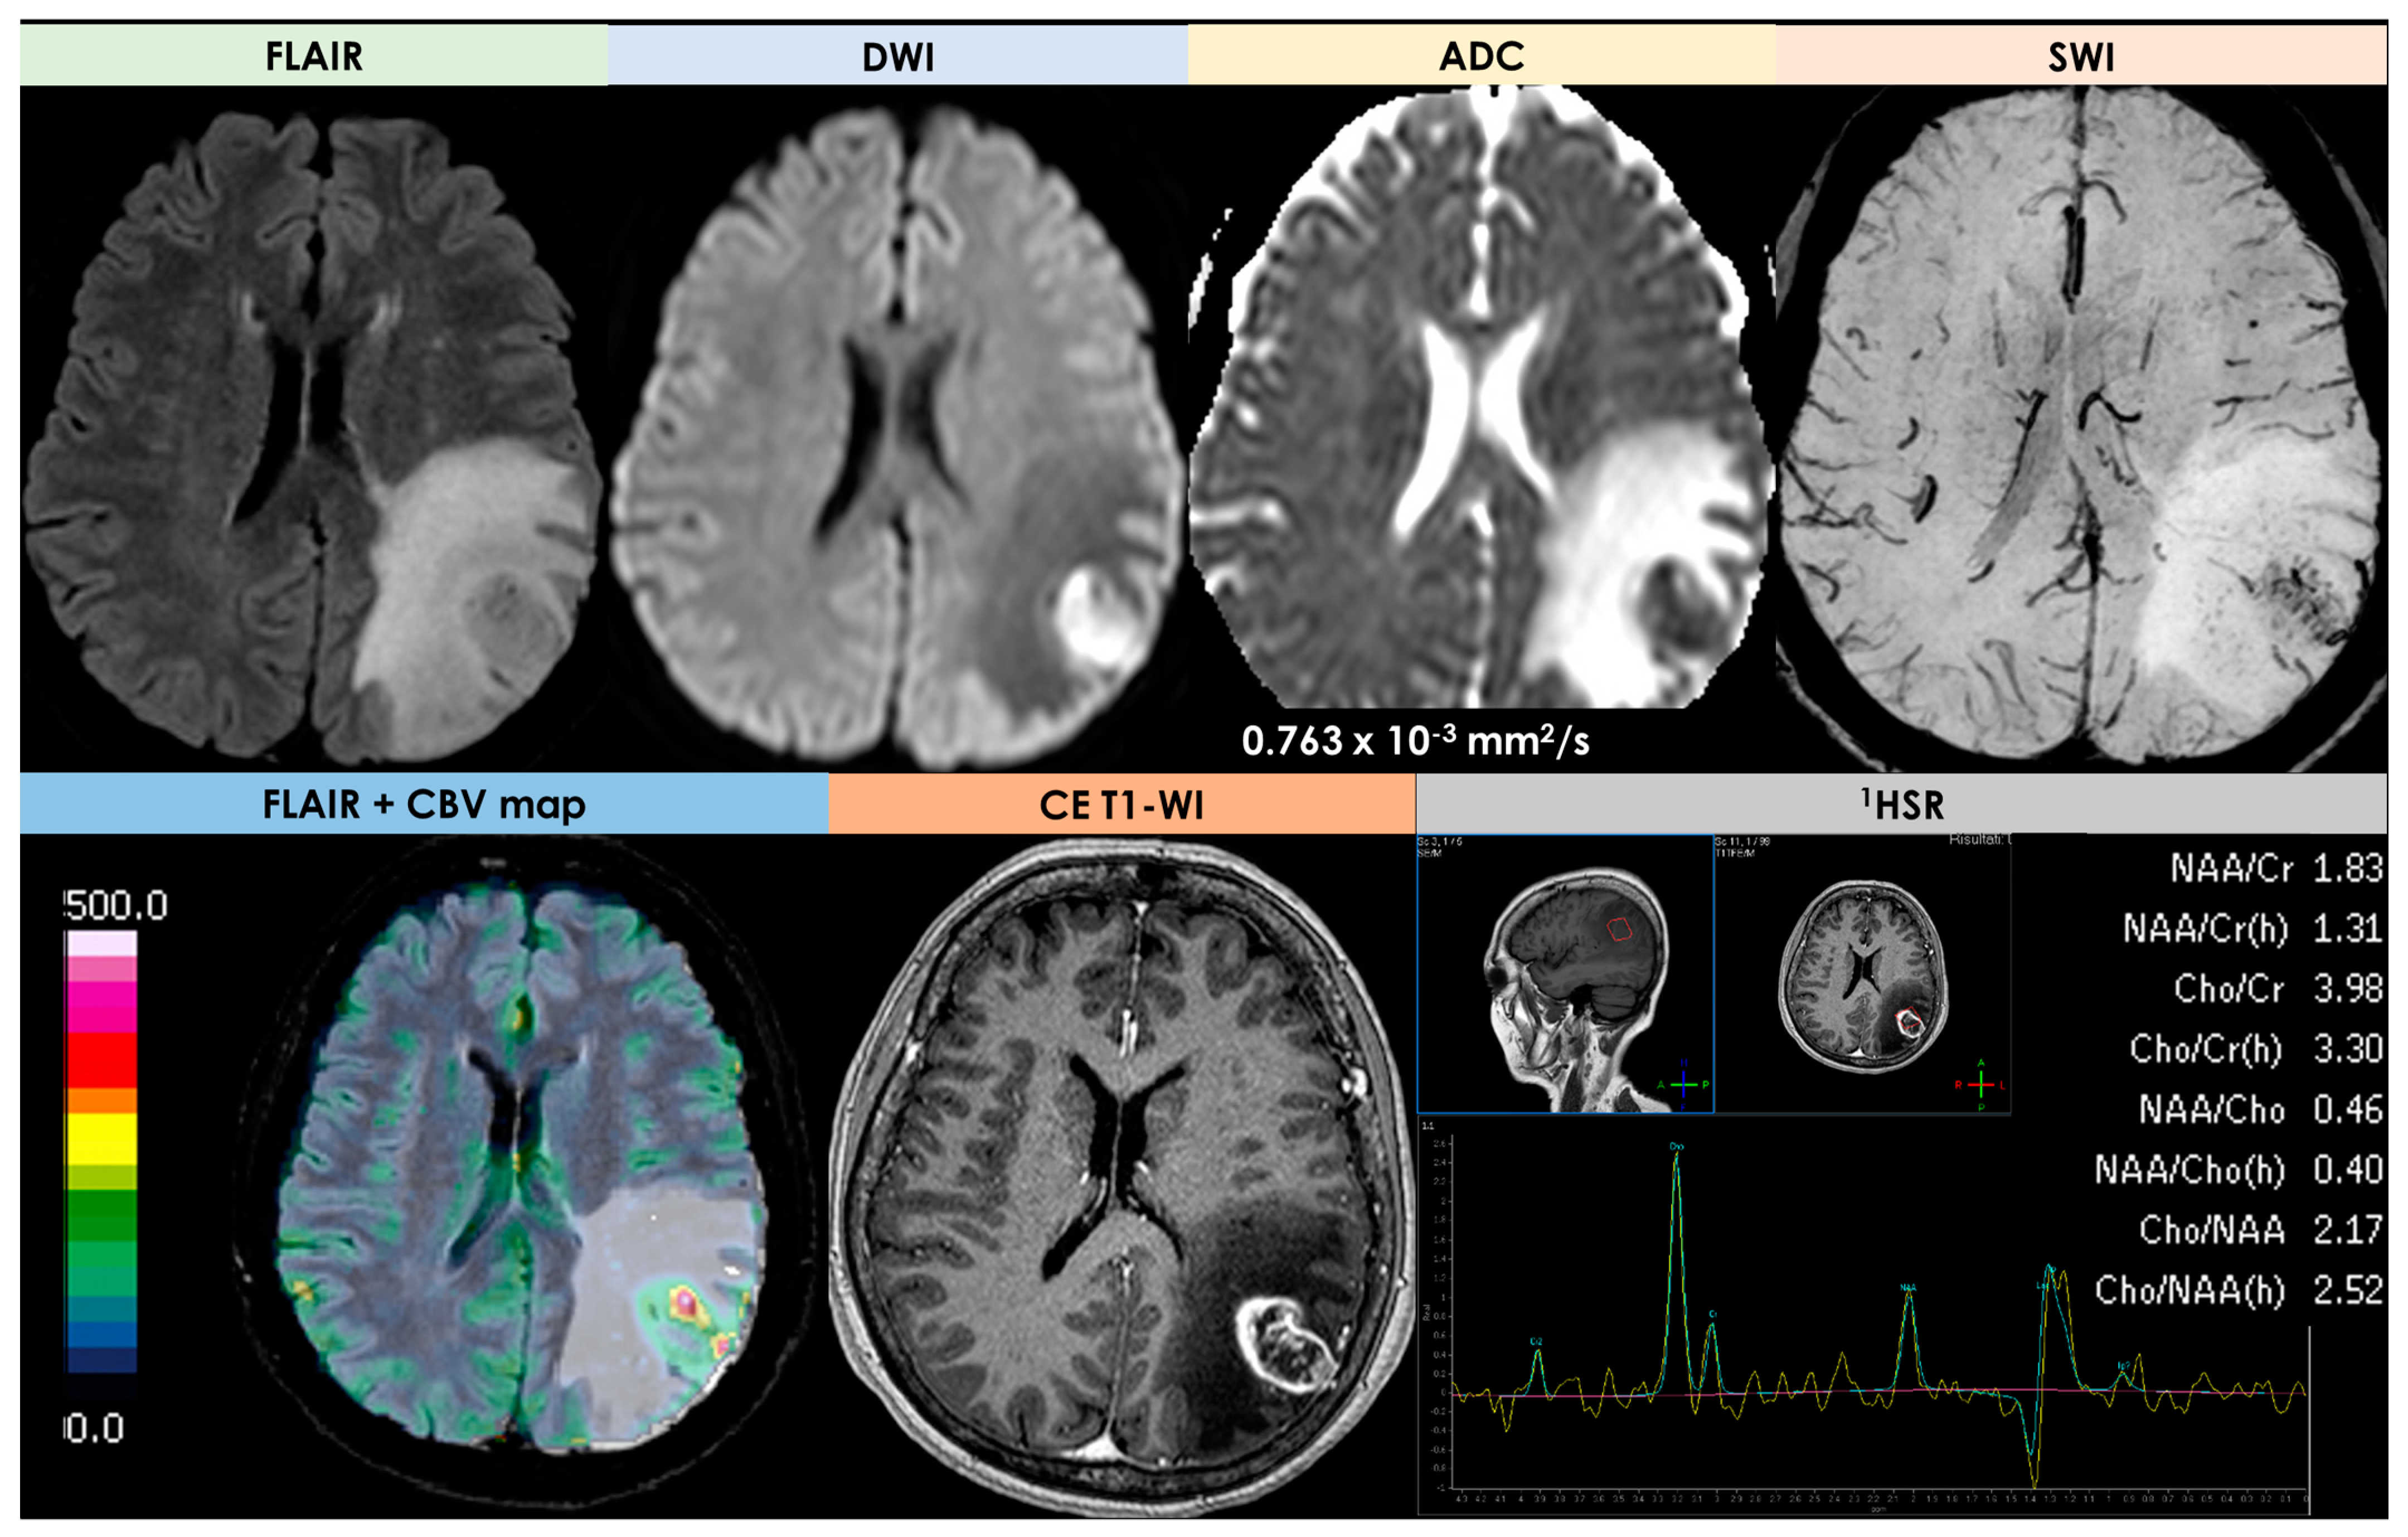

| DWI/ADC | Hyperintense on DWI/hypointense on ADC maps Decreased FA values in lesions | High ADC values in center of lesion and relatively low ADC values in periphery of lesion Threshold for the minimum ADC value for distinguishing TDLs from PCNSL is 0.556 × 10−3 mm2/s | Hypointense in DWI and ADC | Hypointense on DWI and ADC | “Eccentric target sign” consisting of an eccentric nodule along the rim of an enhancing lesion on T1-WI ADC > 1.6 × 10−3 mm2/s suggestive of toxoplasmosis |

| DSC-MRI | rCBV lower than HGG Characteristic TIC | Few data with variable findings | rCBV usually higher than PCNSL, but variable findings | No data | rCBV lower than that in necrotic glioblastomas and metastases |

| Spectroscopy | Elevated lipid peaks and high Cho/Cr ratios | Increased Cho- peak Decreased NAA peak Increased Cho/NAA ratio | Elevated lipid peaks High Cho/Cr ratio | No data | No data |